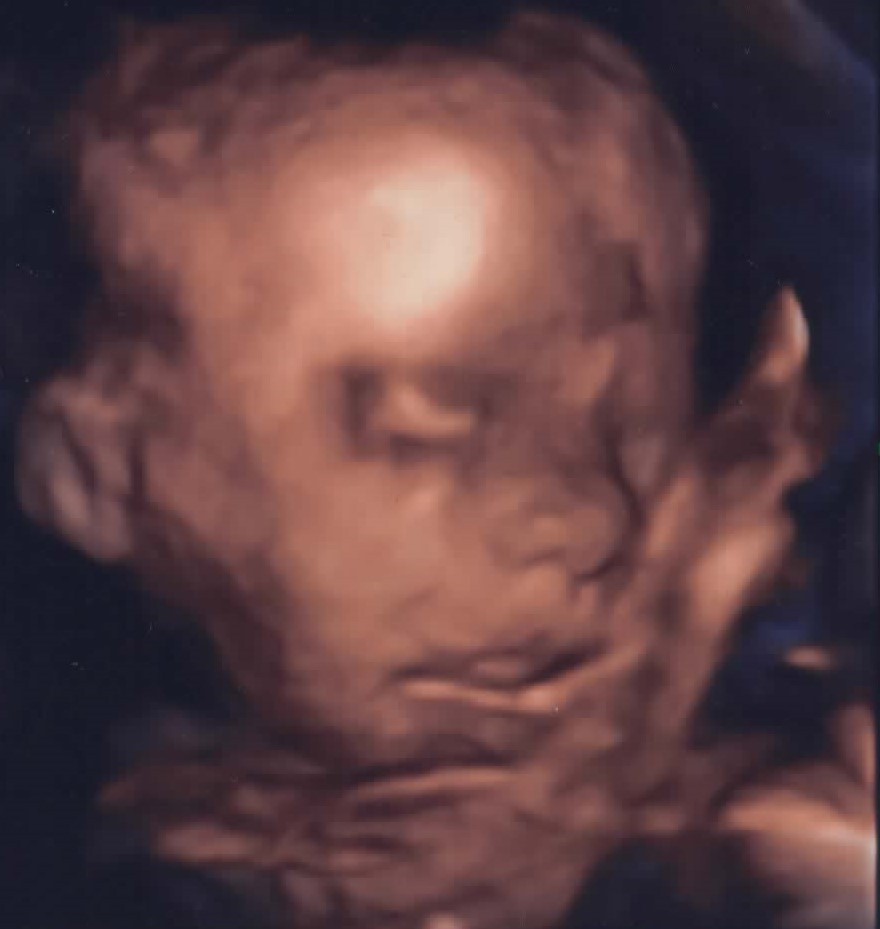

Choć Ignaś jeszcze się nie narodził, to już potrzebuje pomocy lekarzy. Wykryto u niego bardzo złożoną wadę serca, która musi zostać zoperowana w pierwszych dniach życia. Zostały tylko dwa dni na zebranie blisko 180 tysięcy złotych. W wyścigu o życie chłopca liczy się każda minuta i każda złotówka.

Ignaś przyjdzie na świat z wrodzoną wadą serca pod postacią zespołu niedorozwoju serca prawego, przełożenia wielkich pni tętniczych i przerwanego łuku aorty. Jego mama 26 września ma zostać przyjęta do Kliniki Uniwersyteckiej, w Munster, w Niemczech, a obecnie prosi o pomoc w ratowaniu życia nienarodzonego syna.

Wadę serca wykryto w 24. tygodniu ciąży. W najlepszym wypadku maleństwo czekają 3 operacje na otwartym sercu, a pierwsza ratująca życie musi się odbyć zaraz po porodzie, dlatego też poród musi się odbyć w miejscu, w którym zostanie przeprowadzona operacja.